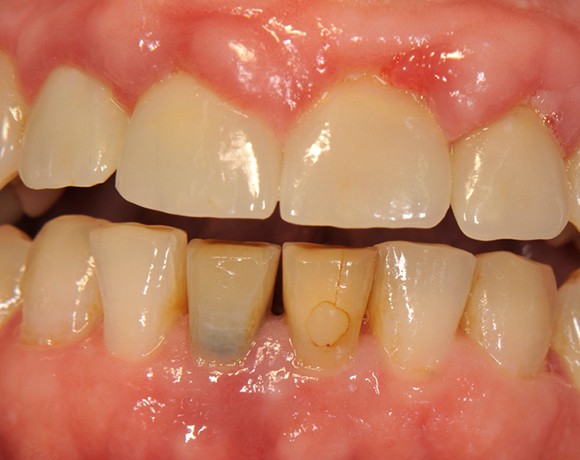

Im vorliegenden Patientenfall wurden die beiden nicht erhaltungswürdigen, mittleren Unterkieferschneidezähne durch zwei Vollkeramikimlpantate ersetzt.